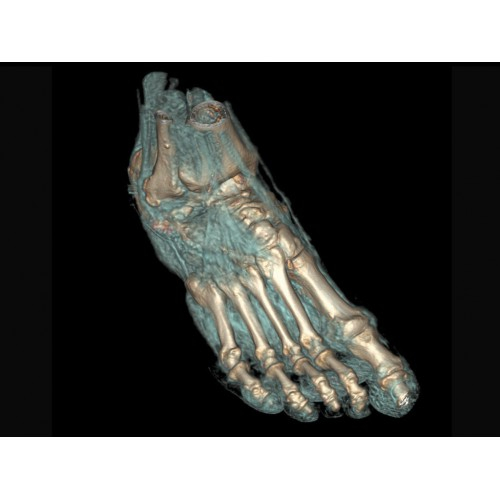

Травматология и ортопедия

• Диагностика сложных переломов и повреждений суставов.

• 3D-реконструкция костных структур для планирования операций.